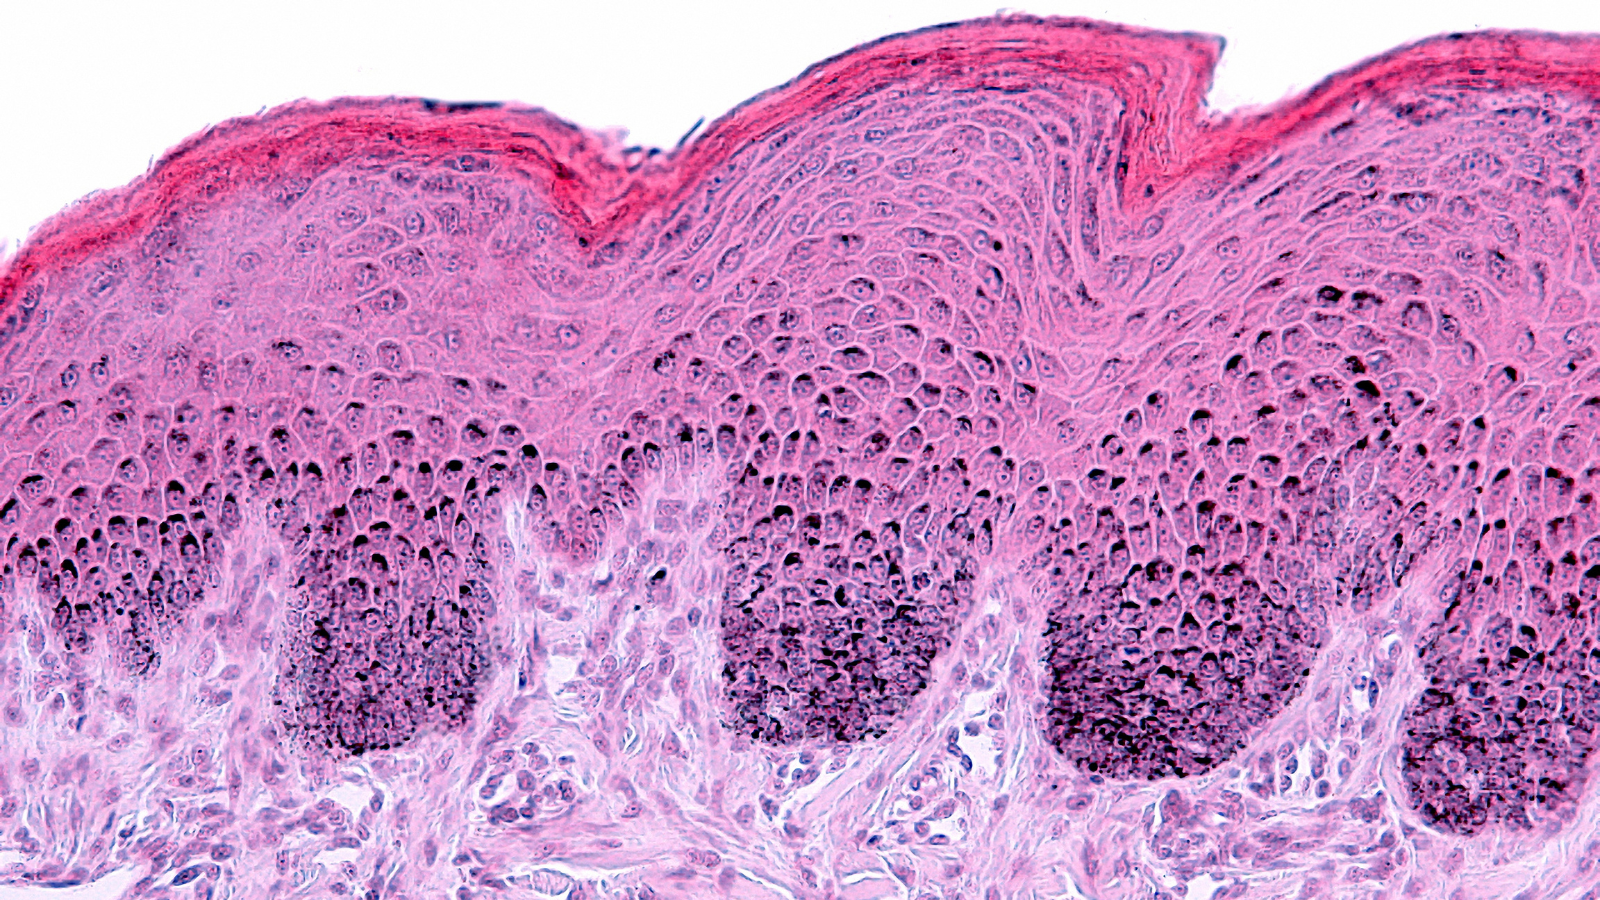

Our new white paper examines the biological drivers of skin aging and details how advanced, non-invasive techniques are transforming clinical evaluation. By combining imaging, biomechanical assessment, biomarker analysis and hydration and barrier function measurements, researchers can now generate multi-dimensional data to scientifically substantiate product claims.